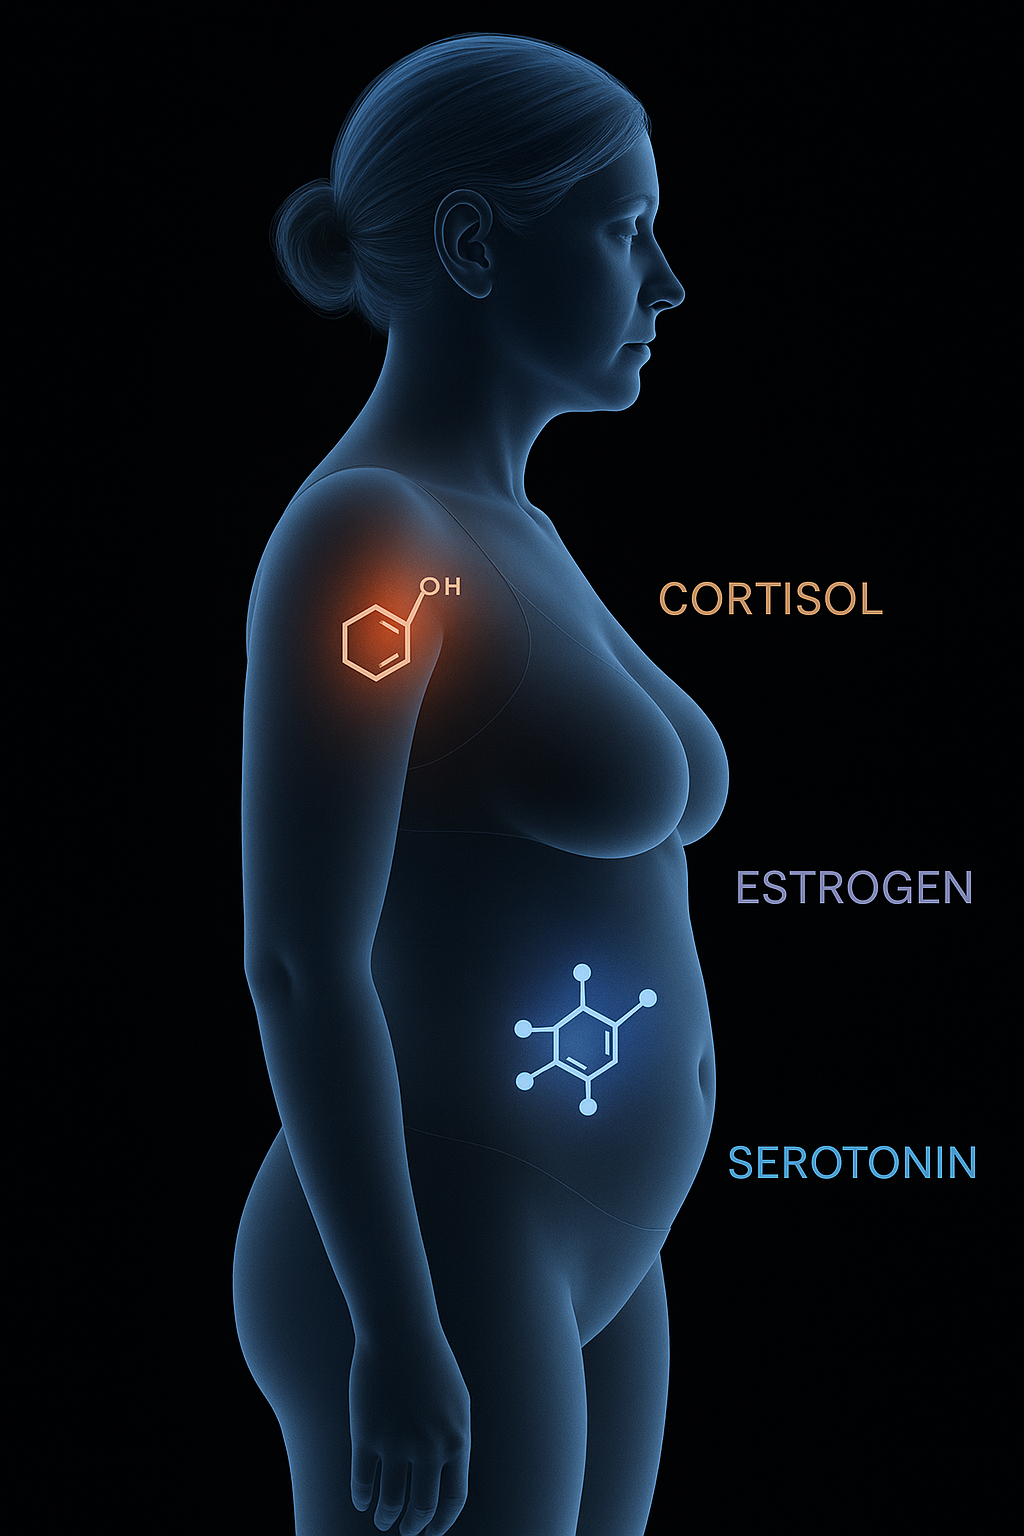

That's why so many women experience:

Now it’s possible to calm your body’s stress response and restore balance from the inside out

How it works?

How it works

How it works